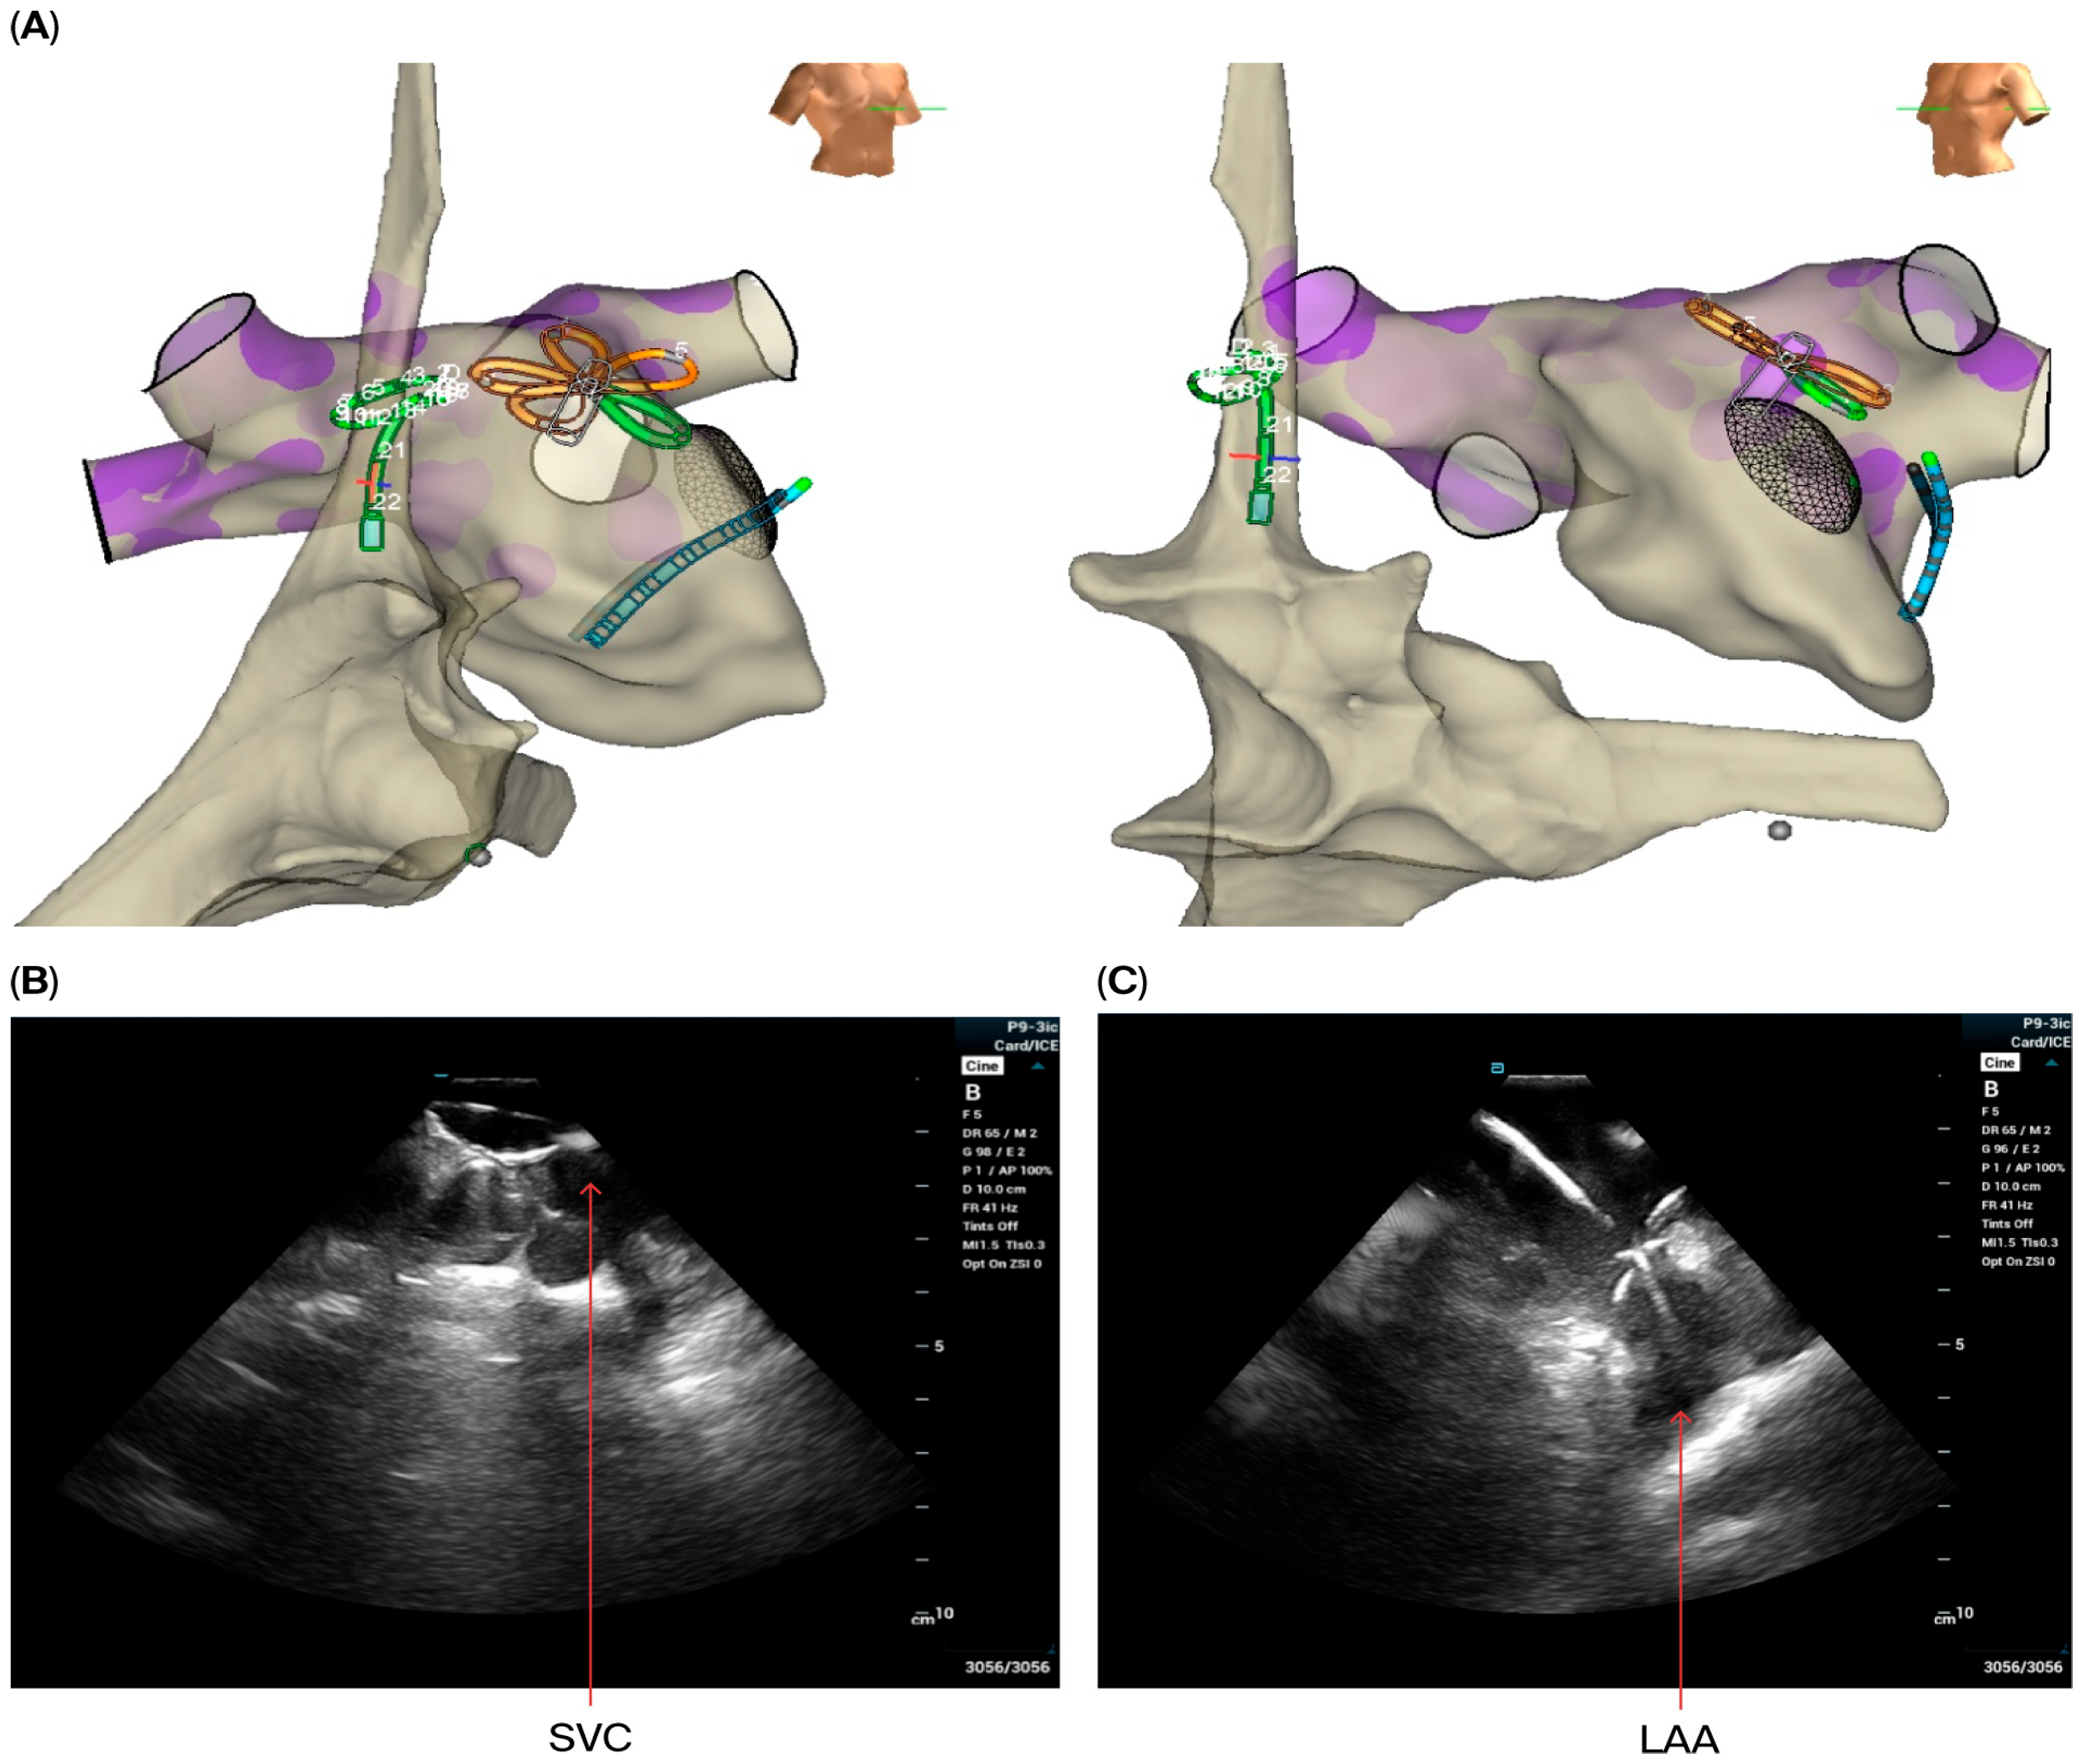

- The VersaCross sheath was exchanged for the Faradrive sheath and dilatator. After predilatation of transseptal puncture, the Faradrive sheath was retracted, and the ICE catheter was advanced along the VersaCross wire to the left atrium (Figure 1A–D). Then, the Faradrive sheath was moved back to the LA, and the dilator and Versacross wire were removed, with the ICE catheter and PFA sheath placed in the LA via a single transseptal puncture.

- ICE images of the LA, including the LAA, were obtained from all patients to exclude LAA thrombus (Figure 1E).

- A circular mapping catheter (CMC) or high-density catheter (with repeated ablation) was advanced to the LA via the Faradrive sheath. Electroanatomic mapping of the LA, including detailed voltage assessment was performed. Then, over the J-tip wire, the Farawave pentaspline catheter was advanced to the LA via the Faradrive sheath. The 0.035-inch J-tip guidewire was attached to the EnSite mapping system’s pin box via a DuoMode extension cable (Boston Scientific, Marlborough, MA, USA) for additional visualization in LA and pulmonary veins. ICE catheter imaging was used to ensure appropriate catheter positioning and catheter–tissue contact with each PV and LAPW PFA lesion delivered. Prior to ablation, 0.2 mg of intravenous glycopyrrolate was administered to all patients to avoid vagal reactions during PVI.

- For superior vena cava (SVC) isolation, the ICE catheter was retracted to the top right of the atrium to guide the ablation procedure. Prior to and after ablating the SVC, the CMC was placed at the junction of the SVC and right atrium to map the phrenic nerve and to detect potential phrenic nerve injury. Then, the Pentaspline catheter was placed at the junction of right atrium and SVC (the lower edge of the right pulmonary artery level in ICE imaging). A total of 4 applications in the basket configuration were delivered (2 followed by 2 other applications after rotating the catheter 30 degree), and heart rate was monitored during the procedure.